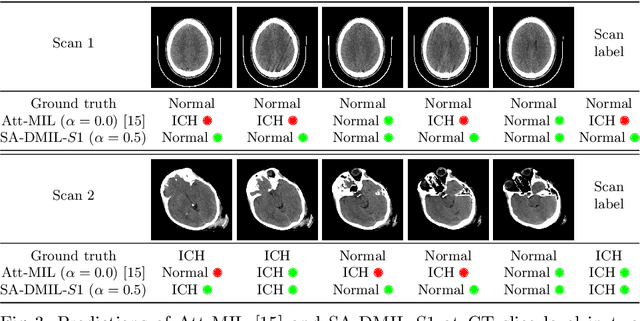

Abstract:Multiple Instance Learning (MIL) has been widely applied to medical imaging diagnosis, where bag labels are known and instance labels inside bags are unknown. Traditional MIL assumes that instances in each bag are independent samples from a given distribution. However, instances are often spatially or sequentially ordered, and one would expect similar diagnostic importance for neighboring instances. To address this, in this study, we propose a smooth attention deep MIL (SA-DMIL) model. Smoothness is achieved by the introduction of first and second order constraints on the latent function encoding the attention paid to each instance in a bag. The method is applied to the detection of intracranial hemorrhage (ICH) on head CT scans. The results show that this novel SA-DMIL: (a) achieves better performance than the non-smooth attention MIL at both scan (bag) and slice (instance) levels; (b) learns spatial dependencies between slices; and (c) outperforms current state-of-the-art MIL methods on the same ICH test set.